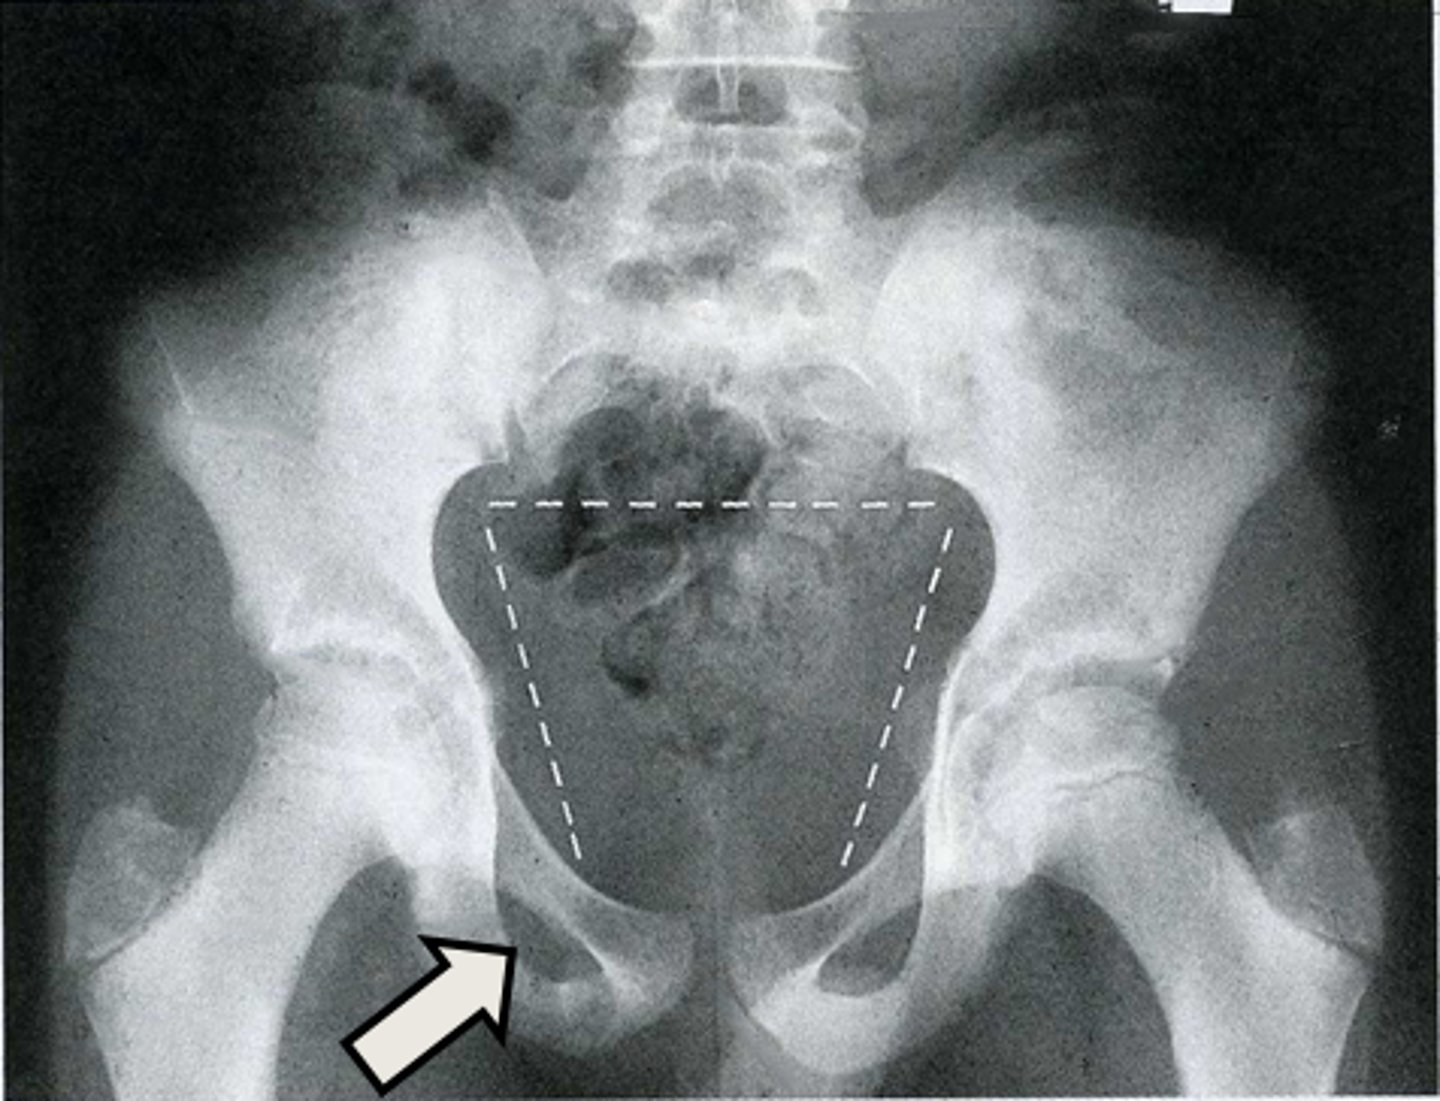

AP pelvis

What is the image?